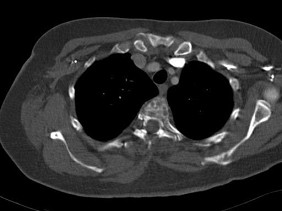

[单选题]女,34岁,咳嗽,咯血半月余,请结合影像学检查,选出最可能的诊断()A.纵隔畸胎瘤B.淋巴瘤C.胸腺瘤D.神经源性肿瘤E.肺癌